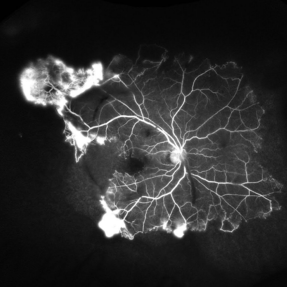

Hemiretinal Vein Occlusion

Nov 14 2024 by Brandon I Fram, MD, BS

40 year-old male with vision changes and observed hemiretinal vein occlusion.

Condition/keywords: branch retinal vein occlusion (BRVO), fluorescein angiogram (FA), Fluorescein angiography, hemi CRVO, hemicentral retinal vein occlusion